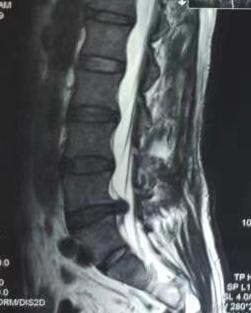

突出椎间盘

张海龙主任医师团队在本例手术中“镜下融合”切口只需1.5厘米。这一手术方式具有切口小、损伤小、可早期下床活动,且术后临床效果与传统切开手术效果几乎无差别、大大缩短住院时间,真正做到了“小伤口解决大问题”,让“爱美人士”也能一步到位“无忧”除病痛。